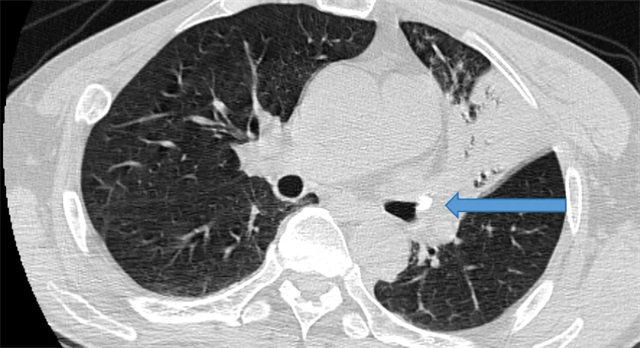

术前CT检查影像

眼见老人身体状况日益不佳,家人急忙带着郑大爷前往信丰县中医院就诊。入院后,呼吸内科医师详细询问病史并进行体格检查,考虑到患者有长期进食呛咳史且咳嗽咳痰症状持续不愈,立即安排胸部 CT 检查。检查结果显示,郑大爷左肺上叶支气管存在异物,且已合并左肺上叶尖后段肺不张,这正是导致他反复咳嗽、咳痰的根本原因。